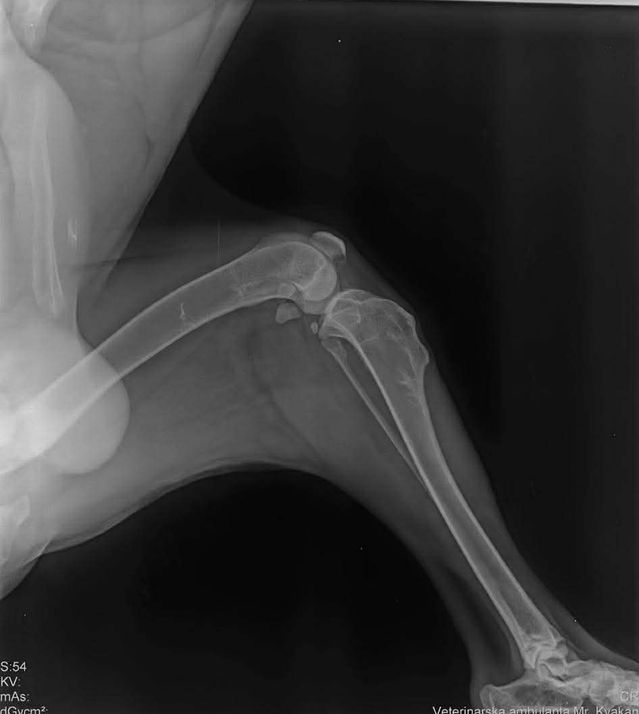

Bemerkungen: Marli hatte eine OP am Knie

Marli kam aus einer Romasiedlung. Er konnte nicht richtig laufen. Der Tierarzt stellte eine alte Knieverletzung fest die dann umgehend operert wurde. Alles ist sehr gut verheilt und heute genießt Marli sein neues Leben.